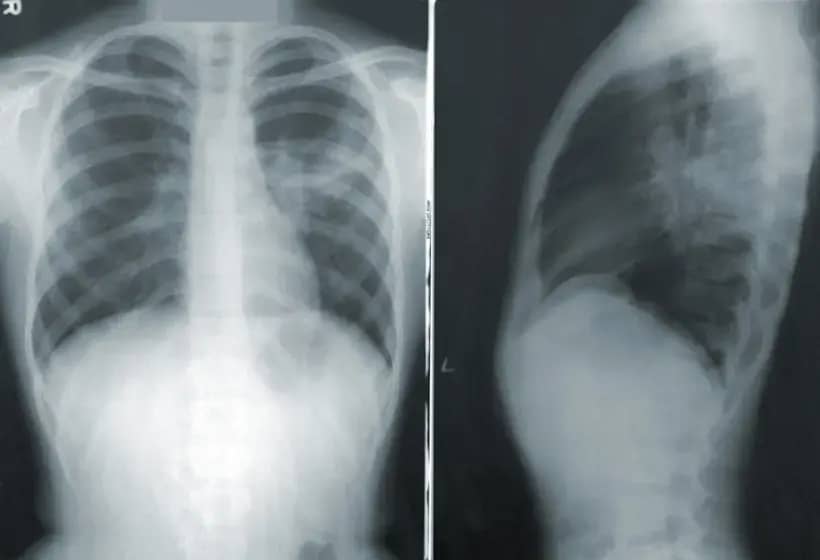

Streptococcus pneumoniae često kolonizuje sluzokožu nosa i ždrela, naročito kod djece; kolonizacija je prisutna kod oko 60 odsto mališana mlađih od dvije godine. Pneumokok može izazvati blaža oboljenja poput zapaljenja srednjeg uha (pogađa gotovo 80 odsto djece do druge godine), ali i teške pneumokokne infekcije kao što su upala pluća, sepsa i meningitis.

Pneumokokna bolest nema jasnu sezonu, ali u jesenje-zimskom periodu, kada su učestale virusne respiratorne infekcije, udružene infekcije dovode do težih kliničkih oblika. Teže forme pneumokoknih infekcija često zahtijevaju hospitalizaciju i unapređenu prevenciju.